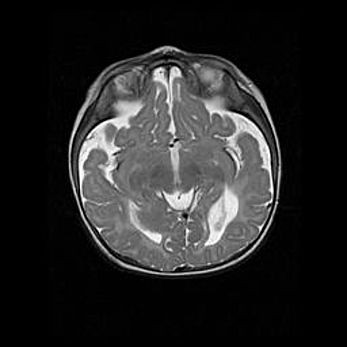

Подострая гематома правой гемисферы мозжечка.

Наружная гидроцефалия.

Возраст: 15 дней

Вес: 3100 г

Пол: женский

Окружность головы: 37 см

Срок гестации: 35-36 недель

При открытой наружной форме гидроцефалии у новорожденных расширяются и переполняются субарахноидные пространства.

Кровоизлияния в мозжечок имеют две клинико-анатомические формы: полушарные гематомы и кровоизлияния в червь.

К появлению этой патологии может привести: повреждения головного мозга, возникающие в результате асфиксии и гипоксии плода при беременности, или травмы во время родов. Редко гематома мозжечка может быть результатом первичной коагулопатии и сосудистой мальформации, диссеминированном внутрисосудистом свертывании, изоиммунной тромбоцитопении.